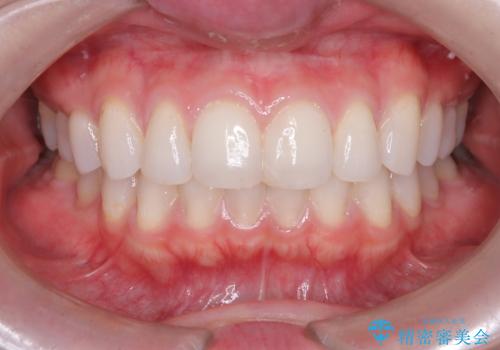

艶感アップになるクリーニング

- 久しぶりのクリーニングで来院された患者様です。

エアフローを行い、着色やバイオフィルム・歯垢(プラーク)が除去され歯の表面に艶が出ました。